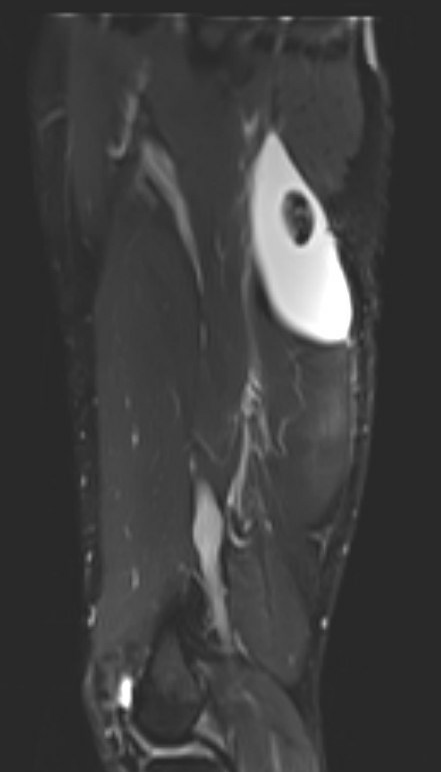

Proximal hamstring tear on right (red circle), normal insertion on tuberosity on left (blue circle)

Proximal hamstring avulsion on right - red circle is retracted hamstring tendon, blue circle is normal insertion on left

Proximal hamstring tear on right (red circle), normal insertion on left (blue circle)

Proximal hamstring avulsion, with tendon floating in hematoma / seroma